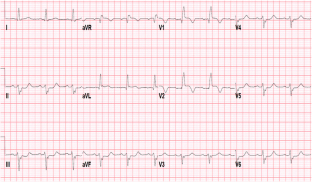

Fractional flow reserve (FFR) is a standardized and well-established method frequently used in clinical practice to evaluate the hemodynamic significance of epicardial coronary stenosis identified by coronary angiography. It is based on the change in the pressure gradient across the stenosis after the achievement of maximal hyperemia of the coronary circulation which is commonly induced by intravenous (IV) or intracoronary (IC) administration of adenosine. Here, we have described three cases of IC adenosine-induced ventricular arrhythmias during FFR measurement from our institution, and after literature review we found that all the cases of ventricular arrhythmias induced by adenosine during FFR measurement were observed where it was administered via IC route. Although a causal relationship between the use of IC adenosine during FFR measurement and the induction of ventricular arrhythmias is not yet established, we suggest using IV adenosine as the preferred route of administration until we better understand the incidence and mechanism underlying this phenomenon.

Raffaele P, Tullio N, Giuseppe G, et al. Adenosine-induced torsade de pointes complicating a fractional flow reserve measurement in a right coronary artery intermediate stenosis. Cardiovasc Revascularization Med. 2013;14:118–20.

Shah AH, Chan W, Seidelin PH. Ventricular fibrillation precipitated by intracoronary adenosine during fractional flow reserve assessment: a cautionary tale. Heart Lung Circ. 2015;11:e173–5.